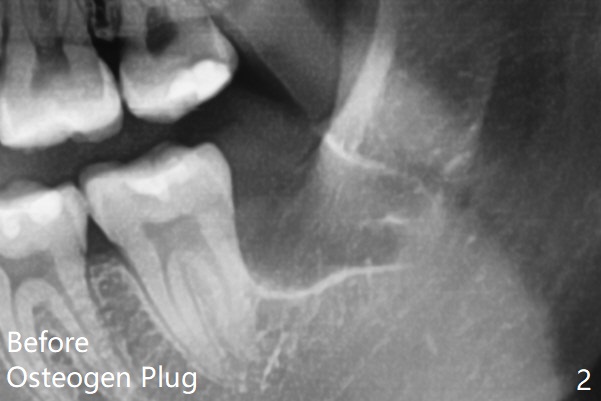

The lower 3rd molar sockets heal in 14 months (Fgi.3).